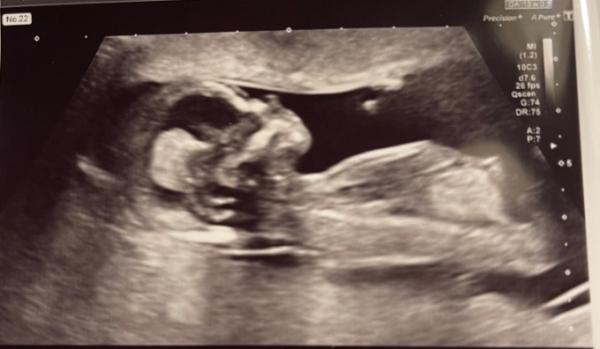

Heute haben wir Ersttrimmester Ultraschall gehabt. Alles sieht super aus. Ich habe mich schon bisschen Sorgen wegen meinem Alter gemacht! Wir sind so erleichtert . Tendenz haben wir auch bekommen. Wir gehören zum Team . Also ich werde mich ganz bestimmt das Video von Ultraschall mehr als 1.235 x anschauen.

Tolles Foto und wunderbare Nachrichten. Da fällt einem doch glatt ein Stein vom Herzen, wenn man hört, dass alles in Ordnung ist. Eine entspannte Kugelzeit weiterhin und Willkommen im Team Blau